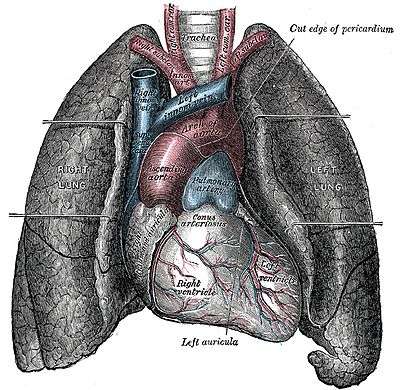

- Lungs

Right and Left Lungs

The Right Primary Bronchus is the first portion we come to, it then branches off into the Lobar (secondary) Bronchi, Segmental (tertiary) Bronchi, then to the Bronchioles which have little cartilage and are lined by simple cuboidal epithelium (See fig. 1). The bronchi are lined by pseudostratified columnar epithelium. Objects will likely lodge here at the junction of the Carina and the Right Primary Bronchus because of the vertical structure. Items have a tendency to fall in it, where as the Left Primary Bronchus has more of a curve to it which would make it hard to have things lodge there.

The Left Primary Bronchus has the same setup as the right with the lobar, segmental bronchi and the bronchioles.

The lungs are attached to the heart and trachea through structures that are called the roots of the lungs. The roots of the lungs are the bronchi, pulmonary vessels, bronchial vessels, lymphatic vessels, and nerves. These structures enter and leave at the hilus of the lung which is "the depression in the medial surface of a lung that forms the opening through which the bronchus, blood vessels, and nerves pass" (medlineplus.gov).